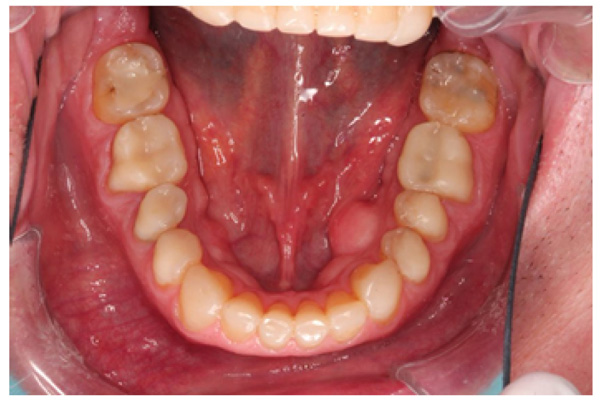

The patient presented with competent lips, an average lip line, normal TMJ function, and a mild Class II Division I incisor relationship with an increased overbite. The preoperative pan-oral radiograph is shown in Fig. (1). Boney exostoses and a large mandibular torus in the lower right mandible were present. The intra-oral presentation of the teeth is shown in Figs. (2-6). The patient had good oral hygiene and a healthy periodontium. The teeth had a glossy, smooth, and glazed appearance, showing cupping of the occlusal surfaces with significant loss of hard tissue and yellow color from the underlying dentine. This presentation was indicative of severe generalized tooth wear with exposed dentine in all sextants. The palatal, occlusal, and incisal surfaces were mainly affected, with lower buccal surfaces exhibiting more wear than the lower lingual, resulting in a reverse curve of Monson. The maximum BEWE score of 18 was recorded, meaning that the tooth with the most severe wear in each sextant had greater than 50% surface loss [9]. Several posterior teeth had amalgam restorations with defective margins (FDI 16, 26, 27, 37, and 47), as shown in Figs. (5 and 6). All teeth responded normally to pulp sensibility tests (cold test). The radiographs did not show any apical pathology to be present, but the pan-oral shows the scooped-out appearance of the lower molars.